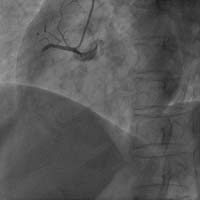

Carto三維定向標測系統(tǒng)指導(dǎo)下房顫射頻消融術(shù)